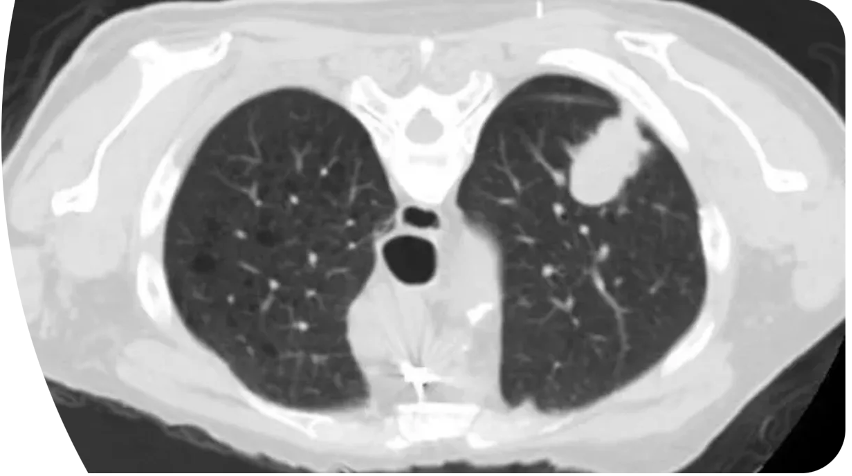

**Lungefibrose**: Karakteristisk: * **Bikagetegning (honeycombing)** (rød pil) * **Traktionsbronkiektasier** (rød cirkel) * Stribeformede fortætninger * Lokalisation: subpleuralt og basalt bilateralt

Diagnose?

Lungefibrose